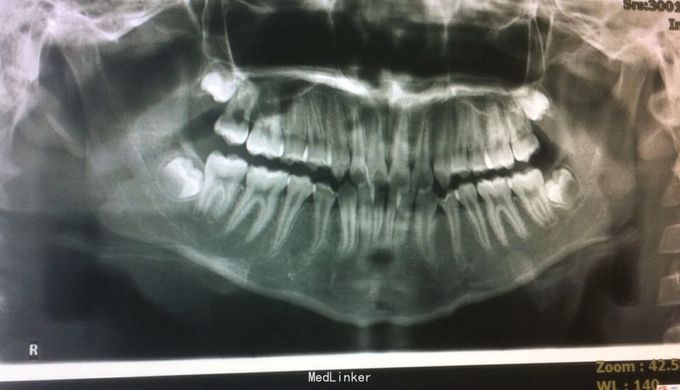

恒牙期 25正锁合 磨牙中性关系 前牙一度深覆盖深覆合 牙列拥挤 张口型异常

安氏一类 不拔牙矫治,直丝弓矫治器,排齐整平上下牙列,治疗后前牙覆合覆盖正常,磨牙中性关系,维持现有面型